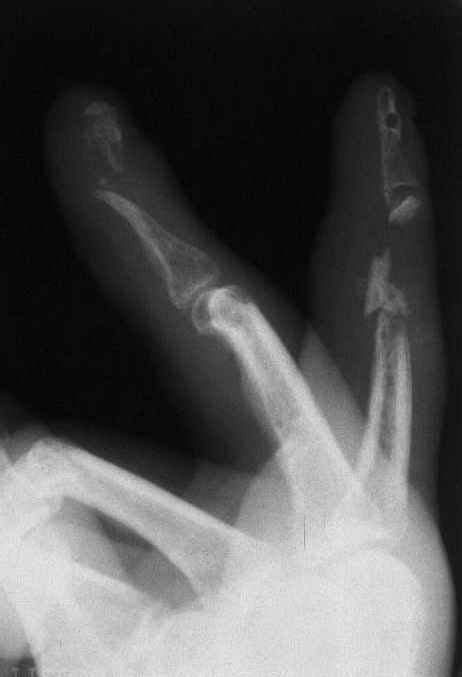

Травма 2,3 пальцев кисти

Уважаемые коллеги! На представленных снимках пальцы правой кисти мужчины 42 года через 3 месяца после травмы циркулярной пилой.

Качательные движения в проксимальном м/ф суставе 3 пальца. Нарушены все виды захвата, в которых принимают участие 2 и 3 пальцы. Кожные покровы с большими рубцами по тыльной и боковой поверхности пальцев. Ни магистральный кровоток, ни микроциркуляция специальными методами не оценивались. Косвенно о трофических нарушениях свидетельствует распространенный остеопороз дистальных фаланг и очаговый остеопороз основных фаланг и головок пястных костей, причиной которого возможно является и длительная иммобилизация в аппарате внешней фиксации. Чувствительных нарушений нет.

Планируем: 3 палец - открытый артродез дистального м/ф сустава с минимальной фиксацией спицей, тенолиз и разработка проксимального сустава (по этому пальцу в общем тактика ясна). 2 палец - обсуждается два варианта тактики:

1. Остеотомия основной фаланги, с последующей дистракцией в аппарате и удлинением последней до дистального м/ф сустава. Далее снова остеотомия - или неартроз, или эндопротез проксимального сустава, тенолиз. (Недостаток - будет потеряно время для восстановления функции сухожилий)

2. Костная пластика средней фаланги, одновременно тенолиз, артродез дистального м/ф сустава, разработка захватов. (Недостаток - опасаемся возможного некроза трансплантата вследствие ангиотрофических нарушений) Буду признателен за высказанные на форуме мнения по поводу пациента.